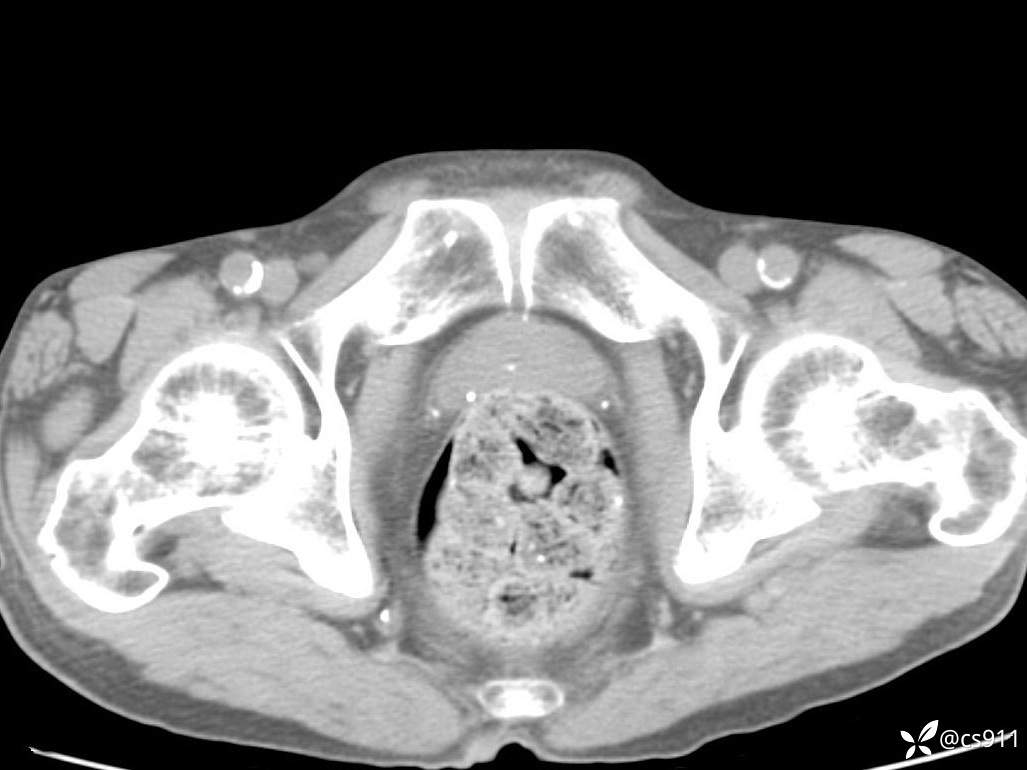

急腹症之急诊CT,原因?答案公布

男,77岁,腹痛、腹胀伴恶心呕吐1天。呕吐胃内容物,非喷射性呕吐,有咖啡色样胃内容物,诉有胃穿孔病史。查体:全腹平,下腹部压痛,全腹无反跳痛,叩诊呈浊音,移动性浊音阴性,肠鸣音减弱,1-2次/分。肛检:直肠未扪及明显肿物,可触及大量粪块。

T 36.6℃ P 80次/分 R 26次/分 BP 100/60mmHg

白细胞(WBC) H 14.55 10e9/L 4-10

红细胞(RBC) 4.58 10e12/L 4.3-5.8

中性粒细胞百分率(NEUT%) H 85.7 % 40-75

血淀粉酶(AMY) HH 1859 U/L 35-135

癌胚抗原(CEA) H 27.44 ng/ml 0-5

呕吐物 潜血试验 * 阳性 阴性

患者轮椅入室检查神志清楚, 能配合摆位和呼吸